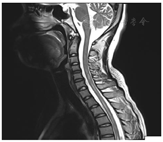

结核药物治疗期间因异烟肼及乙胺丁醇导致视力受损的情况是在临床治疗过程中较为多见的副作用,当患者处于抗痨治疗期间,出现视力损害很容易让临床医生联想到结核药物的影响。但是为什么会在第二次规范抗痨过程中出现视力损害?为什么双侧视力损害不是同时出现?且双侧视力受损程度不一致?在当地医院停用异烟肼、乙胺丁醇后视神经的损害迟迟得不到恢复,是停药时间不够?还是已经出现永久性视神经损害?是否都可以用"药物性视神经损害"解释?或者还有其他原因?带着这样的疑问进行眼科、神经内科、药学部MDT讨论。眼科建议:复查眼底照片、vEP、ERG、FFA、OCT及裂隙灯检查。为除外合并眼结核以及评价视神经是否损害,同时预约眼眶MRI。药学部建议:患者使用的四联抗结核药物中,乙胺丁醇和异烟肼均可能引起视神经病变,其中乙胺丁醇的可能性最大,且其严重程度呈时间和剂量依赖性,早期发现和及时停药可于数周到数月消失,极少数发生永久性视觉功能丧失。同时考虑患者出现结核全身多处转移,抗结核治疗仍需坚持,建议利福平+吡嗪酰胺联合治疗。神经内科建议:完善腰穿、脑脊液及血液送抗水通道蛋白-4抗体检测;同时完善颈胸髓及眼眶MRI(图2、图3),眼眶MRI示双侧视神经鞘膜积液,右侧视神经球后段强化明显,考虑炎性改变。颈胸髓质长段异常信号影。

初步诊断:1.淋巴结结核,培阳,复治,依据:患者有明确淋巴结结核病史,初始治疗疗程不足,本次入院前再次出现颈部淋巴结肿大,淋巴结穿刺培养提示结核分枝杆菌2+,故诊断明确。2.结核性腹膜炎,依据:患者有结核感染基础,曾有不规律治疗史,本次起病存在腹痛、腹水形成,经过抗痨治疗后腹水吸收,故诊断。3.双眼视力障碍原因待查:(1)药物性损害?依据:该患者确诊结核并使用一线方案治疗,抗痨药物中异烟肼、乙胺丁醇可能导致视神经损害,故考虑诊断。但停用结核药物后该患者视力无恢复,仍呈进行性下降,此表现不支持药物性损害特点。(2)眼结核?依据:患者有结核感染基础,前期不规律治疗可能导致结核潜伏,其次结核存在全身多系统感染特征,是否因眼部结核感染导致视力受损需警惕,但眼部MRI成像不符合眼结核特征,支持依据不足。(3)视神经脊髓谱系病?依据:患者视力损害呈进行性加重,起病过程双眼视力损害程度不同,眼部及颈胸髓MRI可见视神经及脊髓异常信号影。脑脊液抗水通道蛋白-4抗体7.15 U/ml(阳性);血清抗水通道蛋白-4抗体80 U/ml(阳性),故诊断明确。